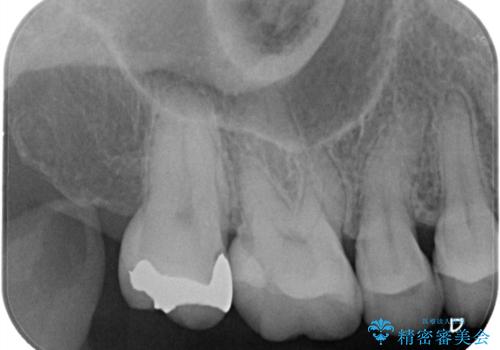

【セラミックインレー】昔治療した詰め物が外れた。

- 他院でいれたセラミックインレーが脱離して、来院されました。

新たに製作を希望されたため、当院で治療しました。

当院でのセラミックインレーの治療は、ラバーダムを使用しています。